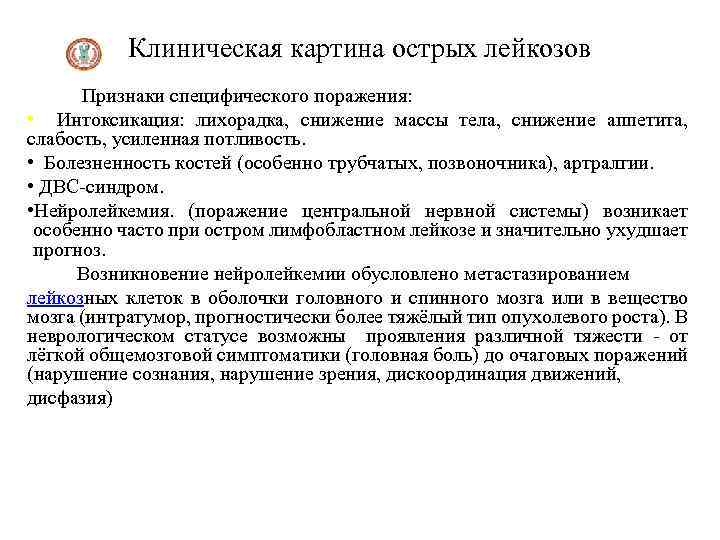

Клиническая картина острых лейкозов Признаки специфического поражения: • Интоксикация: лихорадка, снижение массы тела, снижение аппетита, слабость, усиленная потливость. • Болезненность костей (особенно трубчатых, позвоночника), артралгии. • ДВС-синдром. • Нейролейкемия. (поражение центральной нервной системы) возникает особенно часто при остром лимфобластном лейкозе и значительно ухудшает прогноз. Возникновение нейролейкемии обусловлено метастазированием лейкозных клеток в оболочки головного и спинного мозга или в вещество мозга (интратумор, прогностически более тяжёлый тип опухолевого роста). В неврологическом статусе возможны проявления различной тяжести - от лёгкой общемозговой симптоматики (головная боль) до очаговых поражений (нарушение сознания, нарушение зрения, дискоординация движений, дисфазия)